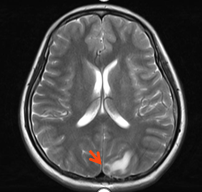

3.头增强MRI:左枕叶强化结节(长径1.3cm,靶病灶2),周围伴水肿,转移可能。(图3)

图3 头增强MRI

2.靶病灶2(脑转移病灶)评效:2周期部分缓解PR,4周期病灶持续缩小,评效PR,6-8周期病灶消失,疗效达CR。(图8)

图8 靶病灶2(脑转移病灶)评效CR